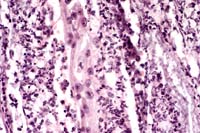

40x

Obj.

- Case 4-2. Kidney. There is multifocal liquefactive

necrosis of medullary collecting tubules characterized by an

infiltrate of neutrophils, histiocytes, and occasional faint

5-10µ yeasts.

- Case 4-2. Kidney. Lumena of necrotic collecting tubules

are filled with pale fungal hyphae and surrounded by neutrophils

and fewer macrophages.

- AFIP Diagnosis: Kidney: Nephritis, necrosuppurative,

multifocally extensive, severe, with necrotizing vasculitis and

numerous fungal hyphae, German Shepherd Dog, canine, etiology

consistent with Aspergillus sp.